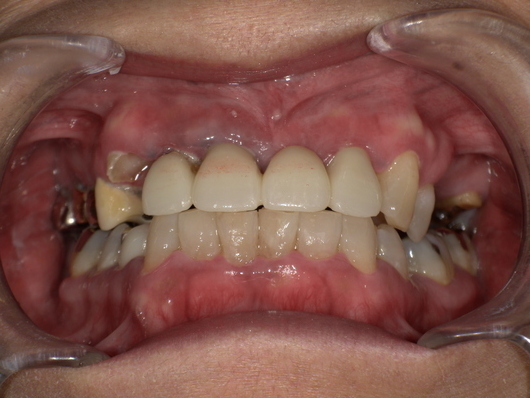

【治療法】口腔扁平苔癬の治し方|薬・生活改善・再発予防まで

ステロイド・免疫調整薬の使用

-

高濃度ステロイド外用薬(ゲルや軟膏など)

重症例には局所用免疫抑制薬(シクロスポリン等)

抗真菌薬、口腔洗浄剤の併用

食生活・口腔ケアのポイント

刺激の強すぎない食事(辛いもの・アルコールなどを控える)

毎日の丁寧な歯磨きと定期的な口腔ケア

適度な水分摂取と唾液の分泌促進

再発を防ぐためにできること

ストレスマネジメント(運動・瞑想・趣味)

金属アレルギーのある方は詰め物の交換を検討

定期的な歯科健診と口腔粘膜のチェック